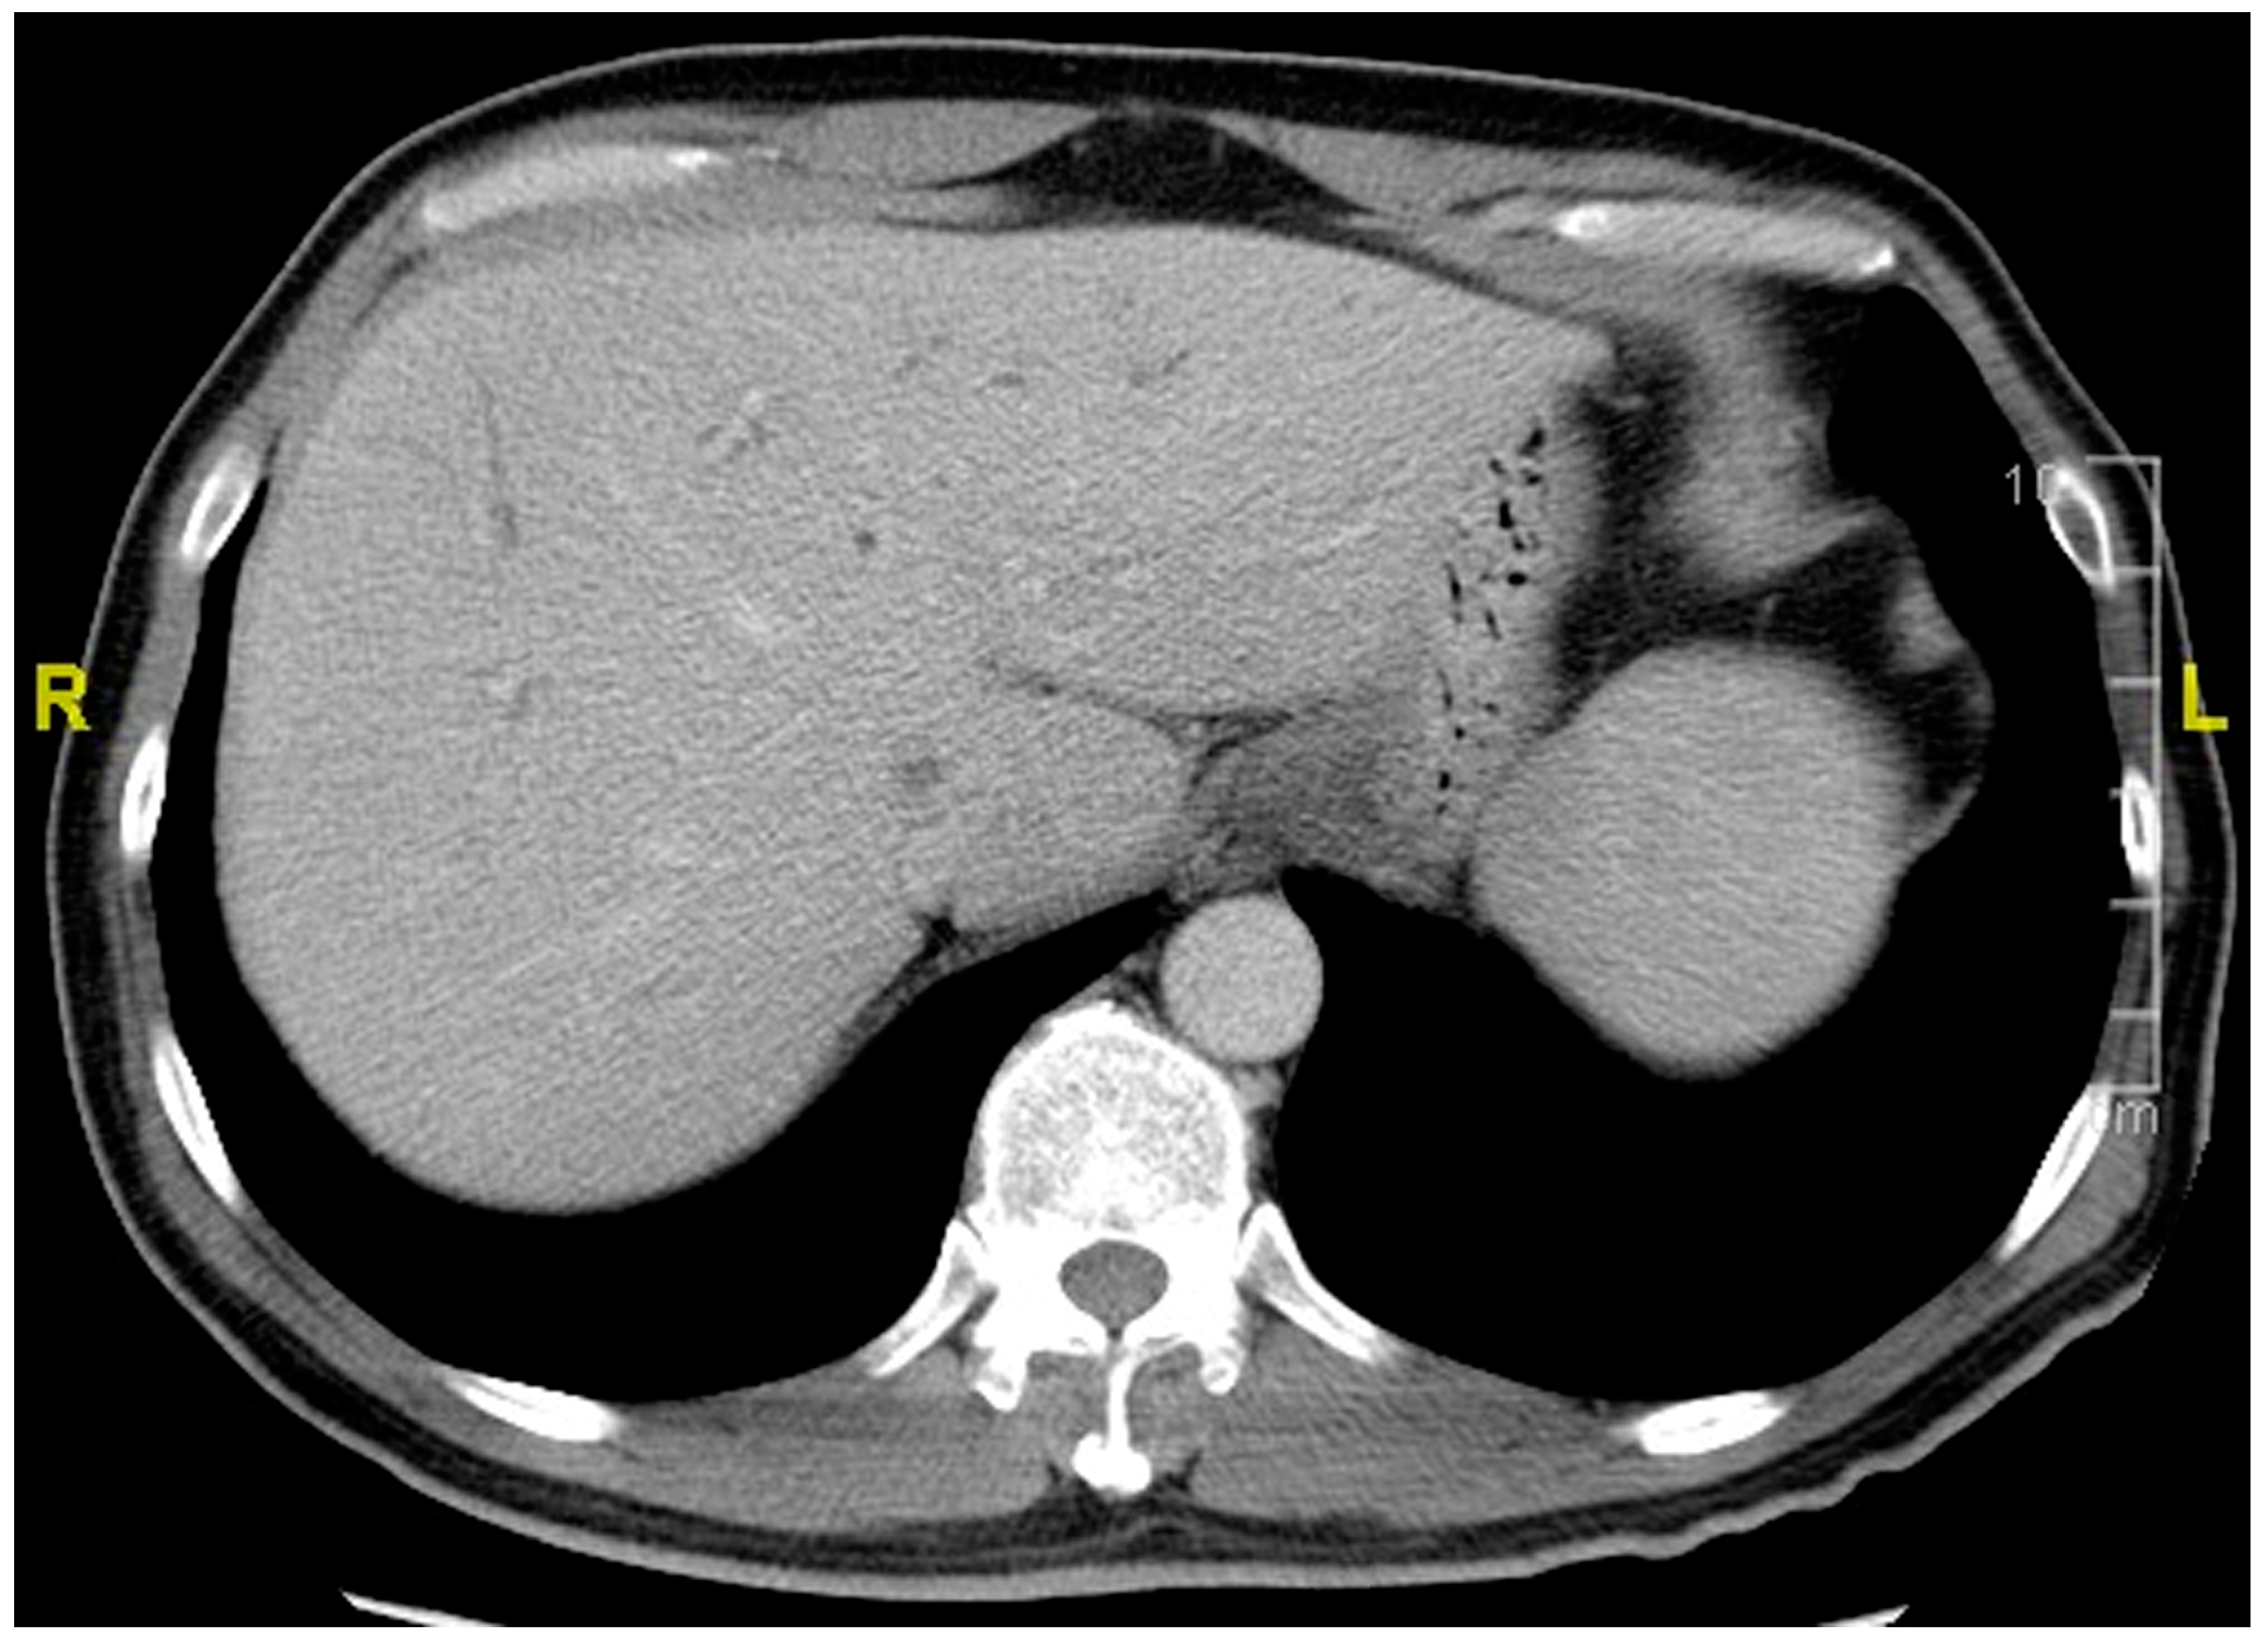

This 59-year-old man suffered from epigastralgia and progressive jaundice for 2 weeks. Tri-phase computer tomography showed diffuse dilatation of intrahepatic ducts (IHDs) with tapering at the hilum (Figure 1). Magnetic Resonance Cholangiopancreatography (MRCP) disclosed diffuse irregular sausage-like IHDs with minimal peri-ductal enhancement and endoscopic retrograde cholangiopancreaticography confirmed a hilar biliary stricture (Figure 2). The SpyGlass™ Direct Visualization System-II (Boston Scientific, Marlborough, MA, USA) demonstrated fibrinous exudates within an ulcerated and erythematous stenotic bile duct. No irregular dilated vessels nor papillary projections were noted, favoring a benign mucosa (Figure 3). POCS-directed biopsy reported chronic inflammation with negative CK AE1/3 staining. Following a 2-month course of ursodeoxycholic acid (15mg/kg/day) for PSC, the patient’s cholestatic-type jaundice normalized. During a three-year follow-up, the patient has been free from recurrent jaundice, cholangitis, and abdominal pain. Notably, both total bilirubin and alkaline phosphatase levels have consistently remained within the normal range, and serial MRCP scans have shown stable results (Figure 4).

Figure 1. Representative computer tomography imaging shows dilated intrahepatic ducts.